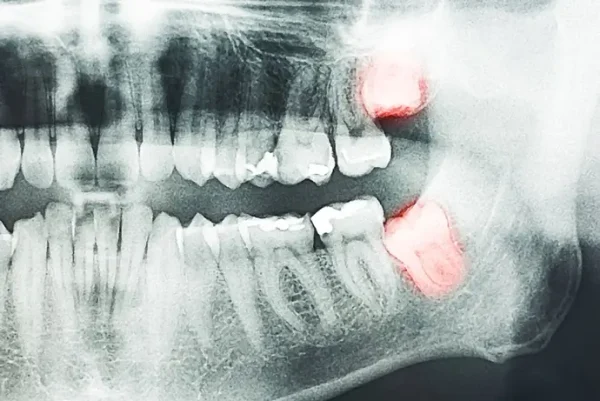

Думаете об удалении зуба мудрости, но боитесь, что потом будет больно? Уже прошли операцию, но болит челюсть после удаления зуба мудрости? В этой статье стоматолог Ковалев Алан Вадимович расскажет, какая боль после удаления восьмерки нормальная, а когда стоит обратиться к врачу. Почему болит после удаления зуба мудрости? Зубы мудрости крупнее других, а также имеют более сложную корневую систему (от 1 до 6 корней). Часто его удаляют по частям. Поэтому это сложная хирургическая операция. При удалении зуба образуется рана, которое заживает около 7 дней. Если после удаления зуба мудрости болит, то это во многом зависит от сложности проведения хирургической операции. Если корни не были сплетены, зуб цел и в ротовой полости не было таких патологий, как периодонтит или пульпит, то риск осложнений минимальный. Если есть искривление, горизонтальное прорезывание, переплетение корней, то экстракция будет более глобальной, а риск осложнений повышается. Есть и другие факторы, которые влияют на боль после операции: Снижение иммунитета. Нарушение техники проведения процедуры. Игнорирование рекомендаций врача, касающихся гигиены полости рта после удаления зуба. Как расположение зуба мудрости может влиять на уровень боли? У нижних зубов мудрости более глубокие корни (расположены ближе к нижнечелюстному нерву). Их удаление часто требует разреза десны или распила зуба (верхние можно удалить только с использованием щипцов). Поэтому боль после удаления нижних восьмерок может быть сильнее и дольше. Почему так больно удалять зубы мудрости? Потому что восьмерки имеют сложную корневую структуру, часто имеют неправильный наклон и могут врастать в соседние зубы. Часто ткани и кость вокруг них очень плотная – требуется глубокое вмешательство. Анестезия не всегда покрывают всю зону. Почему десна болит через 7 дней после удаления зуба мудрости? Потому что могут быть затронуты нервные окончания или долго восстанавливаются поврежденные ткани. Боль более 7 дней может быть признаком инфекции, альвеолита. Рекомендуем обратиться к стоматологу при первых симптомах осложнения. Сколько длится боль после удаления зуба мудрости? При нормальном заживлении тканей и без осложнений боль после удаления зуба мудрости длится 7 дней. После процедуры на месте раны образуется фибрин - сгусток крови, который защищает рану от инфекции и формирует новую ткань. Если осложнений нет, то далее следуют такие этапы залечивания раны: После вмешательства боль начинает проявляться примерно через 3 часа, когда действие анестезии заканчивается. На 3-4 день фибрин начинает преобразовываться в грануляционную ткань. При этом пациент ощущает ноющую боль. На месте вмешательства будет покраснение, возможен отек. На 7 дней боль притупляется, отек проходит. Это свидетельствует о том, что ротовой полости обеспечен нужный уход и проходит заживление. В течение следующих двух недель пациент может наблюдать небольшую болезненность ближе к вечеру. Любой дискомфорт должен пройти через 3 недели. Через 4 недели грануляционная ткань замещается соединительной, которая полностью заполняет лунку. Через 3 месяца на месте удаления образуется костная ткань. Если болевые ощущения не проходят в течение недели, а наоборот боль становится пульсирующей, возникает отек и температура повышается, то срочно нужно идти к врачу. Эти симптомы указывают на осложнения. Боль от осложнений после удаления восьмерки Рассмотрим симптомы, которые могут быть признаками осложнений. 1. Болезненность и кровоточивость десен Основными причинами таких симптомов являются: Травмирование десен во время операции. Процесс восстановления, запущенный организмом, также вызывает болезненные ощущения. Кровоточивость иногда связана с повреждением сосудов в десне. Определенный уровень болезненности является нормальным. Выявить, что кровоточивость и болезненность являются ненормальными, можно по таким признакам: Боль не проходит, становится резкой. Это говорит о том, что в зоне повреждения возникло воспаление. Кровотечение не проходит в течение 48 часов. Это может быть признаком нарушения свертываемости крови, повреждения сосудов и инфекции. 2. Боль в челюсти и ограниченная подвижность Такое может происходить при удалении нижних зубов мудрости, так как они расположены глубоко рядом с крупными жевательными мышцами. Удаление вызывает дополнительную нагрузку на челюсть. Для снятия боли используются противовоспалительные препараты, которые применяются только по назначению врача. Если боль в челюсти и ограничение подвижности сохраняется более 7 дней, то это повод записаться на прием в нашу клинику. 3. Боль в месте удаления Если боль усиливается через неделю после операции, становится пульсирующей, то это может указывать на наличие инфекции. Признаком осложнения при боли в месте удаления может быть резко усиленная, пульсирующая боль. Она может сопровождаться покраснением, отеком. Это является признаком инфекции или развития альвеолита. 4. Боль в соседних зубах Причиной дискомфорта в соседних зубах бывают: Если зуб мудрости был вросшим или находился близко к другим зубам, то во время операции могло возникнуть давление на них. Отек и воспаление в области удаления может распространяться на соседние зубы. Были микротравмы десен во время манипуляций. Это влияет на болезненность зубов, расположенных в зоне травмирования. Жевательная нагрузка изменилась после удаления зуба, что также может вызвать временную болезненность. Затронуты нервы, передающие ощущения в соседние зубы. Наличие инфекции или “сухой” лунки. 5. Боль в ухе Причиной такой боли чаще всего являются нервные импульсы, которые передаются от нижних зубов, расположенных близко к нервам. Такое явление называется иррадиацией боли. Боль в ухе иногда связана с травмой или воспалением. Обратитесь к стоматологу для диагностики, если боль в ухе не проходит более 4 дней и при этом сопровождается отеком и покраснением. 6. Боль в горле и при глотании Часто это связано с отеком или воспалением, которые распространяются и на горло. Для уменьшения боли нужно пить много теплой жидкости, избегать острой пищи и полоскать рот солевым раствором. При усилении боли нужно обратиться к врачу, который исключит инфекцию. 7. Пульсирующая боль Причинами пульсирующей боли может быть инфекция, “сухая лунка”, а также повреждение нервов и перенапряжение тканей. Если пульсация не проходит или усиливается, то стоит записаться к стоматологу. Что усиливает боль после удаления зуба? Усиление боли связано с такими факторами: Сложность операции. Воспаление лунки. Наличие в лунке костного отломка. Повреждение кровеносных сосудов или нервов. При ухудшении самочувствия, появлению налета, гноя, неприятного запаха, увеличении лимфоузлов обязательно нужно показаться доктору. Как облегчить боль после удаления? Можно облегчить боль такими домашними средствами: В первые 48 часов использовать холодные компрессы. Через двое суток компрессы должны быть теплыми. После появления сгустка крови на месте удаленного зуба рекомендуется промывать его соленой водой. Для облегчения боли можно использовать обезболивающие препараты, которые уменьшают воспаление. Принимать их следует только после консультации с лечащим врачом. В период восстановления важно организовать себе больше отдыха, уменьшить физическую нагрузку, особенно первые два дня после операции. В качестве продуктов стоит выбирать жидкую и мягкую пищу в виде супов, соков, пюре, смузи, йогуртов. На период реабилитации лучше отказаться от острой еды, которая вызывает дискомфорт в ротовой полости. Если после удаления зуба мудрости болит нижняя челюсть и воспаление не проходит больше недели, то это может быть причиной инфекции. В таком случае нельзя тянуть с посещением врача. Вопросы-ответы Нормально ли, что после удаления зуба у меня повышается температура? Да, повышение температуры является нормальной реакцией организма на хирургическое вмешательство. Но если температура не снижается больше 7 дней, то обязательно нужно идти к врачу. Как избавиться от кариеса самостоятельно? Моя щека опухла. Нормально ли это? Отек щеки является нормальным после получения травмы. В большинстве случаев он проходит в течение 7 дней. Если на 5-ый день пациент замечает увеличение отека, покраснение, выделение гноя, увеличение интенсивности боли, то это является поводом звонить в клинику. Когда можно начинать чистить зубы в области удаления? Чистить зубы после процедуры удаления нужно с осторожностью. В первые 24 часа нельзя ни чистить зубы, ни полоскать рот. Со второго дня можно аккуратно чистить зубы, избегая поврежденной области, чтобы не переместить сгусток. Через 7 дней можно вернуться к нормальной чистке зубов, но к зоне повреждения нужно по-прежнему относиться осторожно. Рекомендуем использовать щетку с мягкой щетиной. Что делать если не могу открыть рот после удаления восьмерки? Это явление, называемое тризм, распространенное. Оно появляется из-за воспаления тканей зуба или жевательных мышц. Для облегчения состояния в нашей клинике мы рекомендуем прикладывать к щеке теплые компрессы на 15 минут в день, делать гимнастику, плавно открывая и закрывая рот, а также соблюдать диету с мягкими продуктами, не требующими жевания (йогурт, пюре, смузи). Если стоматолог прописал противовоспалительные препараты, то можно их принимать. В течение 3-х дней рот должен начать постепенно открываться. Если этого не происходит, а появляется отек, покраснение, то нужно обратиться к врачу. Может ли болеть кость челюсти после удаления восьмерки? Да, это возможно, особенно при проведении сложных операций. Такая боль вызвана травмами кости, воспалением тканей или мышечным напряжением. Причиной боли может стать и инфекция, поэтому если боль не проходит больше недели, то рекомендую записаться на прием в нашу клинику. Как ускорить заживление после удаления зуба мудрости? Чтобы ускорить заживление раны после удаления восьмерки, необходимо строго относиться к указаниям врача в отношении гигиены.